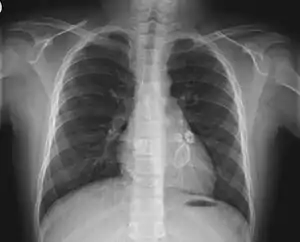

![]() | |

| کودکی با زبانی به رنگ توتفرنگی و دون دون شده، قطع نشدن تب قاچ خوردن، لب هاو پوست پوست شدن بدن از نشانههای سندروم کاوازاکی است. | |